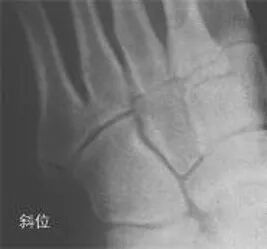

30°斜位上:1、第四跖骨内侧缘和骰骨内侧缘连续成一条直线2、第三跖骨内侧缘和外侧楔骨内侧缘连续成一条直线3、第二、三跖骨基底间隙和内、中楔骨间隙相等。

2005年Pearse等提出“ABC”的方法来阅读足部X 线片, 以减少中、前足的漏诊。 A ( alignment)检查跖骨与相应楔骨的对应线 B ( bone)检查每一块骨的轮廓 C ( congruity )检查整体一致吻合, 在正位片上观察内柱, 在斜位片上观察中、外柱。侧位片的常规检查可发现Lisfranc关节矢状面的半脱位及撕脱性骨折